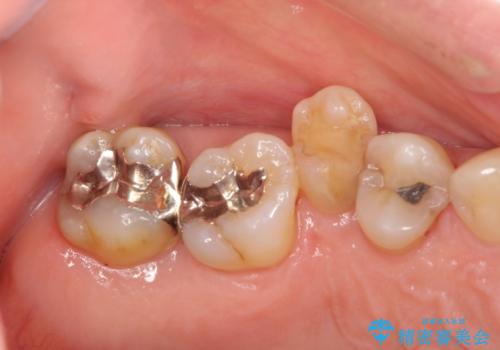

- 歯のぐらつき、歯周病の検査を希望され来院されました。

検査の結果、強い歯ぎしりによる歯の周囲の骨の吸収が認められたため歯槽骨の再生・歯周ポケットの除去・力に対抗する連結補綴・補綴前処置としての小矯正を計画します。